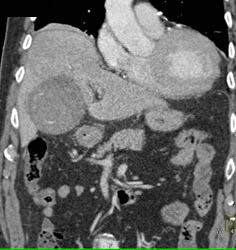

Focal Nodular Hyperplasia (FNH)